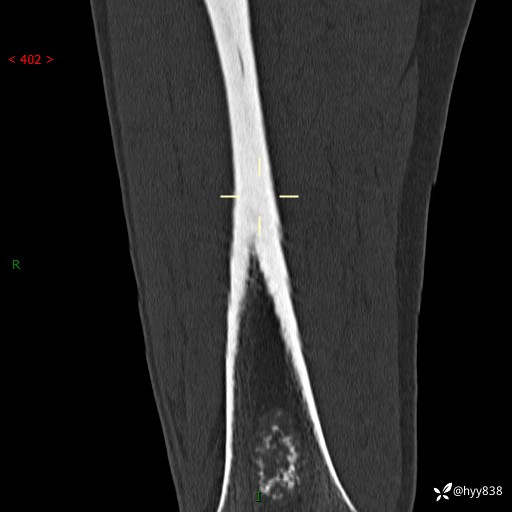

CT

img